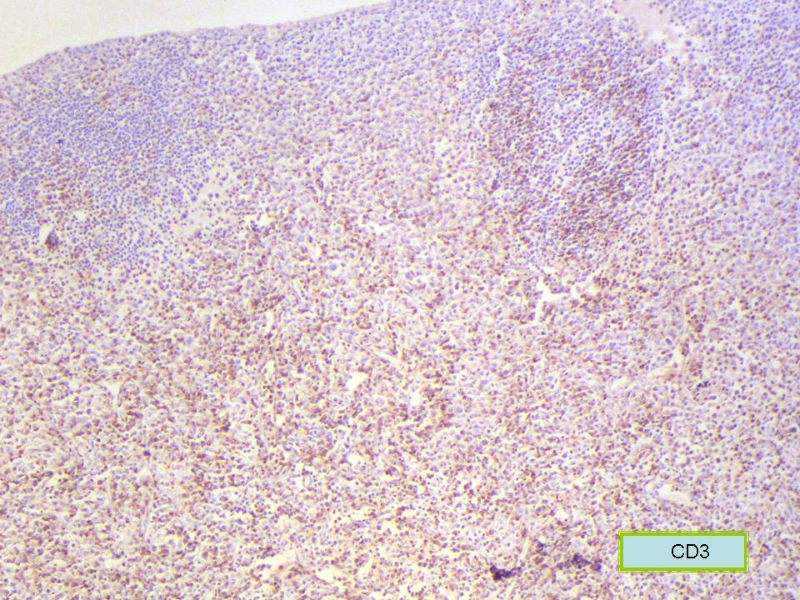

该患者可能存在病毒的感染,抑或是EB病毒的感染,包括CD30+的细胞在内,夹杂在组织细胞、小淋巴细胞之间的一些个大细胞是活化的淋巴细胞,表型看来属B细胞。整个形态呈反应性增生的形态。

总之,现有的图片显示的形态和IHC标记尚不足以诊断为淋巴瘤,除非有有基因重排的支持。

请看下图,显示的细胞比较杂,胞浆较丰富,胞核没有什么特别的异型性。没有促纤维增生反应和围血管生长表现,没有肿瘤性坏死,没有见到更多的核分裂,特别是病理性核分裂。因此认为,本例是淋巴组织反应性增生,可能是对病毒感染的反应。